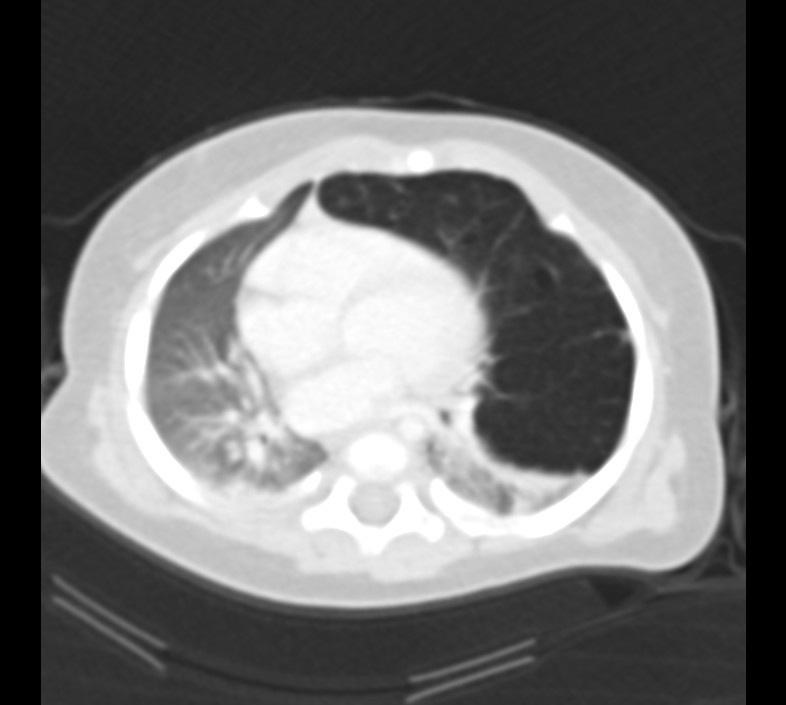

What pulmonary disease is this patient likely to develop?

Kartegners Syndrome